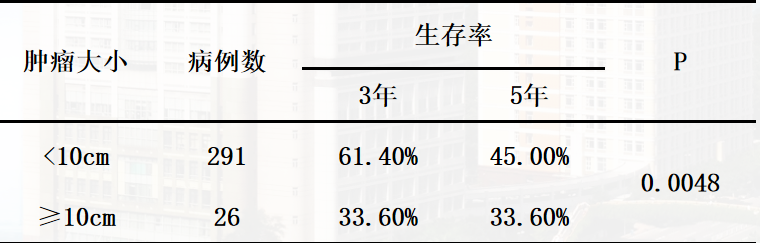

原发性肝癌能手术切除者仅占10%~15%,由于巨块型肝癌多数合并血管侵犯和肝内播散以及肝功能不全,手术切除危险性和难度更大,手术切除率更低,只能进行姑息性切除。Taniai N报道≥10cm的肝癌术后生存率明显低于<10cm的肝癌。